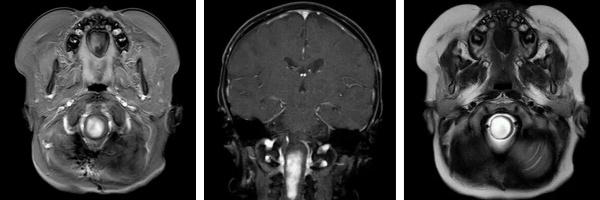

术前影像(MRI)

怀着最后一线希望,阿什利一家跨海越洋,来到我院脑肿瘤科求助。入院时,患儿右侧肢体活动严重受限,面瘫症状逐渐显现。影像检查显示肿瘤位于脑干中央,与周围重要神经结构和血管关系密切,手术难度极大、风险极高。